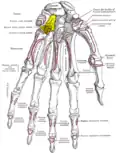

Bones of the left hand. Palmar surface. Hamate shown in yellow.

Bones of the left hand. Palmar surface. Hamate shown in yellow. -